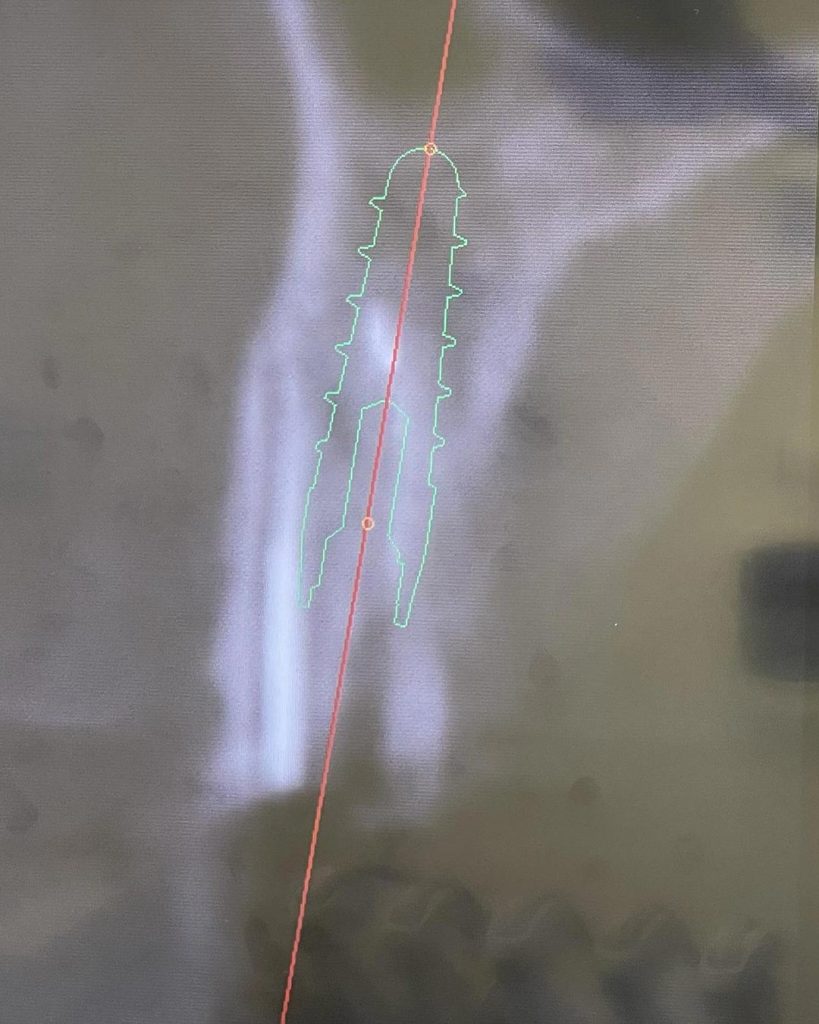

Nelle immagini è possibile osservare la radiografia iniziale, la radiografia post-operatoria e la TAC pre-chirurgica con la progettazione dell’impianto.